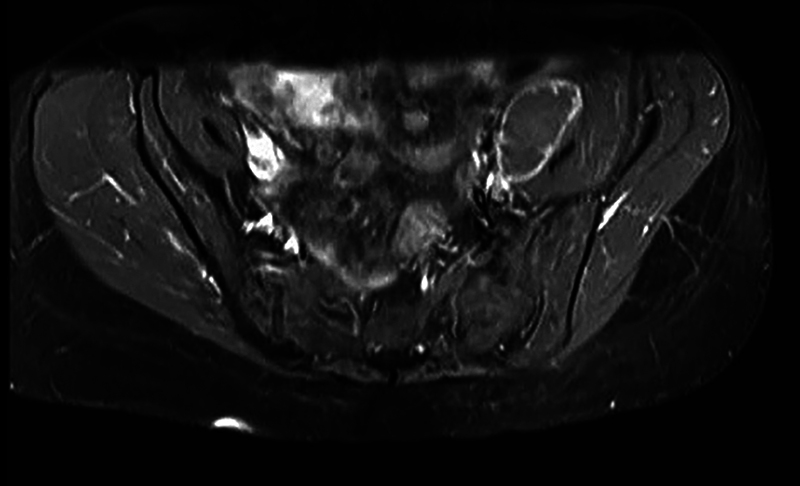

结核病(TB)是一种由结核分枝杆菌复合体引起的慢性感染,在影响免疫系统的情况下,如多发性硬化症,以及用疾病缓解药物(dmd)治疗结核病,结核病再激活的风险增加。本研究是一项回顾性研究,对1994年2月至2023年9月期间在圣保罗联邦大学圣保罗医学院神经内科和神经外科诊断为多发性硬化症的2036例患者进行了随访。其中6例纳入本病例系列,服用不同的dmd: fingolimod (n = 2)、干扰素β 1a (n = 2)、醋酸格拉替默(n = 1)和环磷酰胺(n = 1)。在我们的研究中,两名患者在结核病治疗过程中残疾加重,另外三名患者在完成治疗后残疾加重。我们强调筛查所有符合DMD治疗条件的患者的重要性,特别是高效的现代治疗,以及制定基于研究的MS患者传染病筛查指南的重要性。

Tuberculosis (TB), a chronic infection caused by the Mycobacterium tuberculosis complex, has an increased risk of reactivation in conditions that affect the immune system, such as MS, and its treatment with disease-modifying drugs (DMDs). The present is a retrospective study of 2,036 patients diagnosed with MS followed at the Department of Neurology and Neurosurgery of Escola Paulista de Medicina, Universidade Federal de São Paulo, from February 1994 to September 2023. Of that total, 6 were included in this case series, taking different DMDs: fingolimod (n = 2), interferon beta 1a (n = 2), glatiramer acetate (n = 1) and cyclophosphamide (n = 1). In our study, two patients experienced worsening disability during tuberculosis treatment, while three others had increased disability after completing treatment. We reinforce the importance of screening all patients eligible for DMD treatment, especially the highly effective modern ones, and the importance of developing research-based guidelines for screening infectious diseases among patients with MS.